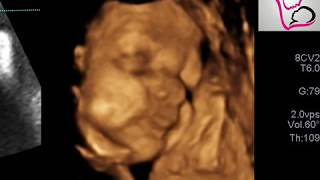

شكل الجنين في الشهر الثامن في السونار

جنين ذكر في الشهر الثامن سونار رباعي الأبعاد Youtube

شكل الجنين في الشهر الثامن الذكر